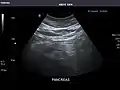

Pancreas

Pancreas: Visualized portions unremarkable.